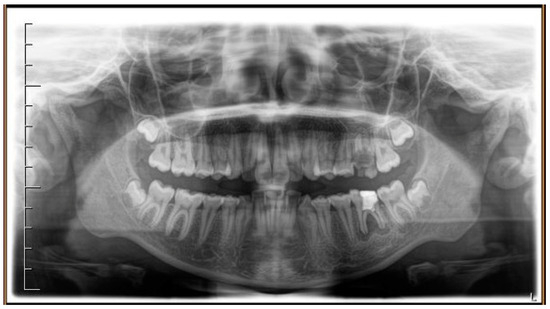

Figure 1.

Pre-treatment radiograph of the patient. The first two left molars appear irreparably compromised by destructive caries.

A case of CA therapy without attachments and without the aid of hybrid elements has been documented. The patient, an 18-year-old woman at the beginning of treatment (October 2021), signed written informed consent to orthodontic treatment and authorized the use of her anonymized treatment data, including photos, X-rays and virtual models of the dental arches. She needed to rehabilitate two edentulous areas corresponding to first maxillary and mandibular molars, both on the left side, assessed as irrecoverable for destructive caries at the time of the orthodontic evaluation (Figure 1). The patient refused rehabilitation with prosthetic implants and orthodontic treatments with fixed or hybrid fixed-removable therapy. Orthopanoramic (Figure 1) and lateral teleradiography of the skull (Figure 2) were acquired to make the necessary assessments. The cephalometric examination was performed using the Cephio© Cephalometric Analysis artificial intelligence driven platform (Cephio sp. z. o. o. [Ltd.]). Her skeletal class II malocclusion was due to maxillar and mandibular retrusion (SNA 80°, SNB° 74.6°, ANB 5.4°, SNPog 76.2°). She had “long face” (OP-SNP 21.1°), a posterior inclination of the jaw (MPGoGn- SNP 35.4°), slight hyperdivergence (FMA 26.2°), with pro-inclined lower incisors (1-NB 28.4°, IMPA 96.1°) and retroclined upper incisors (1-NA 14.1°, FMIA 57.7°). Overjet and overbite were severely altered (6 and 7 mm) (Table 3). Orthodontic treatment started 4 months after the first left maxillary and mandibular molar extractions. Intraoral and facial photos were captured (Canon© Coolpix A900, Canon, Tokyo 146-8501, Japan). Dentally, she had a first molar and canine class on the right side, and a first canine class on the left side in which the molar class was no longer assessable (initially it was a first class); however, a partial reduction in edentulous spaces was observed due to the movement of adjacent teeth (Figure 3) and lower incisors were moderately crowded. Precision silicone impressions (Elite HD+ Putty Soft Normal and Elite HD+ Super Light Body, Zhermack SpA, Badia, Italy) were taken using the double technique. Then, a virtual setup of the treatment with CAs was developed to evaluate its feasibility. It showed full closure of edentulous spaces and was also discussed successively with the patient. The orthodontist clarified there were no data from the literature (at that time) to support the successful movements required with only CAs. The orthodontist and patient started treatment by agreement. The informed consent to treatment was signed. It also covered clinical re-evaluation with solutions less favorable to the patient’s preferences if the results in the middle of treatment had been clinically unsatisfactory or unfavorable. The orthodontist explained the need to intercept any treatment complications to the patient. This also related to the predictability of intermediate results for medico-legal reasons, for the mutual protection of her as a patient and of the orthodontist as a professional responsible for the therapy. Initial and final virtual models were superimposed to evaluate the movements obtained (Maestro 3D©, AGE Solutions S.r.l., Pontedera- Pisa, Italy). At the end of the therapy, new X-rays were requested and new intraoral and extraoral photos were recorded.